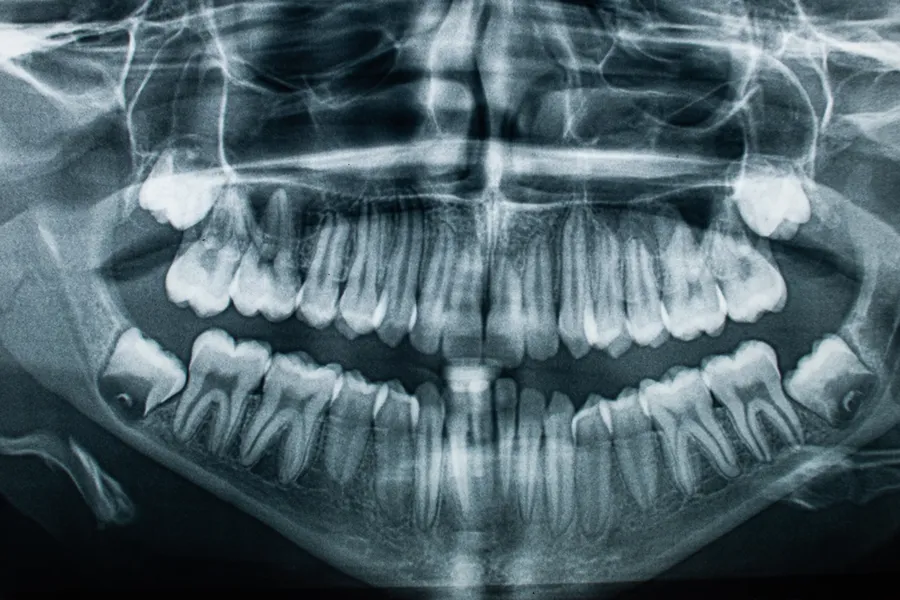

Tanngraderingen som går inn i BioAlder, blir gjort av to tannleger ut ifra et ortopantomogram (OPG), som er et panoramabilde av hele kjeven. Dersom tannlegene seg i mellom er uenige, blir en tredje tannlege involvert.